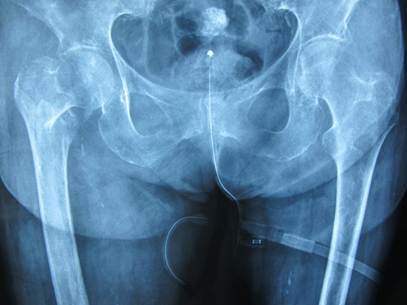

Ταξινόμηση καταγμάτων ισχίου

Στην ορθοπαιδική, τα κατάγματα του ισχίου κατηγοριοποιούνται με διάφορα συστήματα. Για την καλύτερη κατανόηση από τον ασθενή ο πιο πρακτικός διαχωρισμός είναι σε δύο βασικές κατηγορίες:

- Ενδοαρθρικά

- Εξωαρθρικά

ή αλλιώς

- Υποκεφαλικά

- Διατροχαντήρια

Η επιλογή της αντιμετώπισης τους στηρίζεται στον παραπάνω διαχωρισμό, στον τύπο του κατάγματος αλλά και στην κατάσταση της υγείας και της κινητικότητας του πάσχοντος.